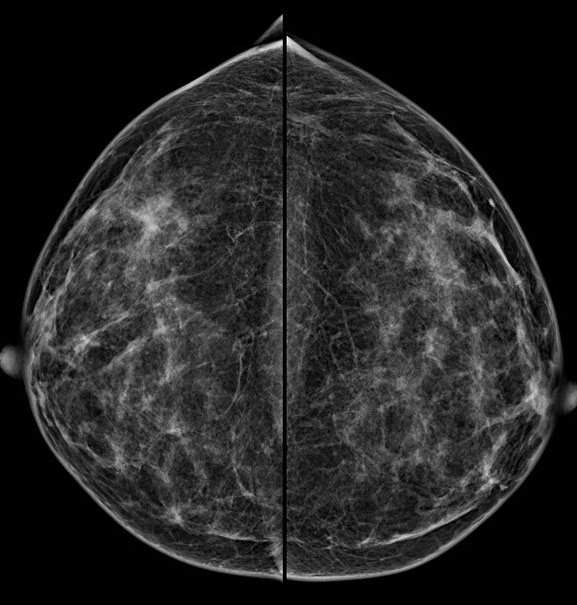

Bei der Mammographie handelt es sich um ein Röntgenverfahren, welches auf einem einfachen Prinzip beruht: Unterschiedliche Gewebestrukturen (Fettgewebe, Bindegewebe, Brustdrüsengewebe) haben eine unterschiedliche Dichte. Die bei der Mammographie verwendete weiche Strahlung wird von einzelnen Gewebekomponenten unterschiedlich absorbiert, woraus unterschiedliche Kontraste im Mammographiebild resultieren.

Mit dieser digitalen Vollfeld-Mammographie – wie sie in der Radiologie Graz St. Peter für Ihre Brustuntersuchung eingesetzt wird – ist ein entscheidender Fortschritt in der Mammographiepraxis gelungen. Die neuen Flat-Panel-Röntgendetektoren bieten eine extrem hohe Quantenausnutzung und ein hohes Auflösungsvermögen.

Dadurch resultieren eine geringere Dosis (Strahlenbelastung) und eine bessere Bildqualität, welche auch zu einer etwas höheren Brustkrebsentdeckungsrate führt.

2.  Bessere Aussagekraft bei dichtem Brustdrüsengewebe

Vor allem junge Frauen bzw. Frauen vor der Menopause haben ein dichtes Brustdrüsengewebe. In der konventionellen Mammographie ließ sich dieses dichte Gewebe oft schlecht darstellen. Aufgrund von Fehlbelichtungen waren Wiederholungsaufnahmen notwendig, die eine zusätzliche Strahlenbelastung mit sich brachten. Die digitale Mammographie kann hingegen auch geringere Kontraste in sehr dichtem Brustdrüsengewebe deutlicher hervorheben und so eine zuverlässigere Diagnostik ermöglichen. Fehlbelichtungen wie bei der alten konventionellen Mammographie werden praktisch ausgeschlossen.

3.  Exaktere Bildanalyse – sicherere Diagnose

Durch die höhere Kontrastauflösung bei einem höheren Kontrast-Rausch-Verhältnis wird die Erkennungsrate von malignitätsverdächtigen Veränderungen deutlich verbessert. Der Radiologe kann auf hochauflösenden 5 MP-Monitoren die Dichte, Form und Kontur von Gewebearealen wesentlich exakter differenzieren und so gutartige von bösartigen Herdbefunden sicherer unterscheiden. Im Speziellen sind Mikroverkalkungen auch bei der dichten Brust besser zu analysieren.

Die Diagnosesicherheit und Möglichkeit einer Brustkrebsfrüherkennung durch die Mammographie, hängt von der Dichte des Brustdrüsengewebes ab. Einteilung der Dichtegrade wurde vom American College of Radiology (ACR) übernommen.

Bei einem Dichtegrad 3 sinkt die Sensivität der Mammographie deutlich, bei Dichtegrad 4 liegt sie unter 50 %. Durch gleichzeitigen Einsatz der Ultraschalluntersuchung wird die Sicherheit in der Diagnoseerstellung jedoch wieder auf

ca. 90 % angehoben.

40 % der Mammakarzinome weisen Mikroverkalkungen auf. Mikrokalzifikationen sind auch bei sehr dichtem Brustgewebe immer sichtbar. Eine Mammographie sollte daher ab dem 40. Lebensjahr die primäre Untersuchungsmethode sein.